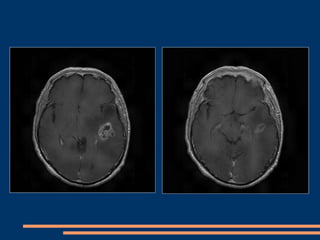

IRM post-opératoire à J 15

IRM post-opératoire à 3 mois

IRM post-opératoire  3 mois

CAS CLINIQUES –GIESSEN+CHU FORT de FRANCE Patient de  35  ans  (GIESSEN) Ralentissement  psychomoteur depuis 1 mois , déficit moteur de l’hémicorps droit d’installation progressive , aphasie  de Wernicke et Broca. Juin 2009 : réalisation d’une IRM cérébrale montrant un glioblastome temporal profond gauche avec effet  de masse. Opéré avec GLIOLAN couplé au Pentero avec option fluoroscopie.

IRM pré-opératoire

IRM pré-opératoire (suite)